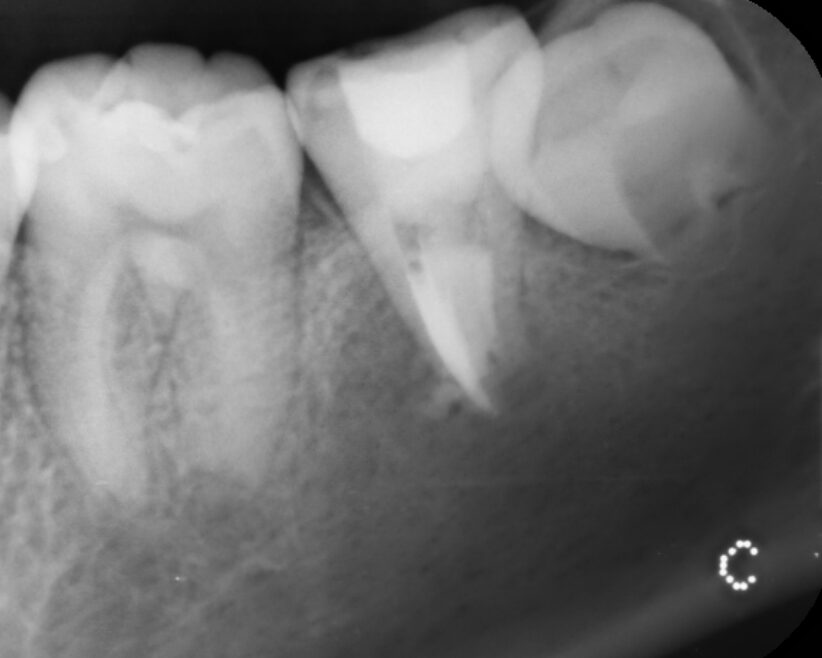

当医院は、保存治療専門の歯科医院です。精密根管治療により根管の感染を徹底的に除去し、膿の改善をはかりました。画像は、根管充填時のレントゲン写真です。雨樋状に根管を清掃し、根の先までしっかり根管充填しました。